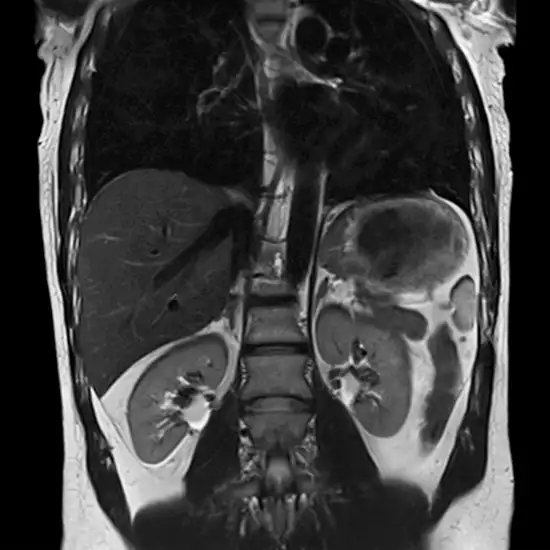

MRI Abdomen with Contrast examines any abnormal liver function test or kidney function test findings to determine the origin of abdominal pain or swelling.

• To check for stomach, kidney, liver, pancreatic, or spleen masses or enlargements

• To evaluate liver or kidney abnormalities.

• Assess kidney disorders, such as infections, swelling (hydronephrosis), stones, and malignancies.

• To evaluate liver disorders (infections, fatty liver, cirrhosis).

• To identify suspected liver, kidney, spleen, or other abdominal cancers.